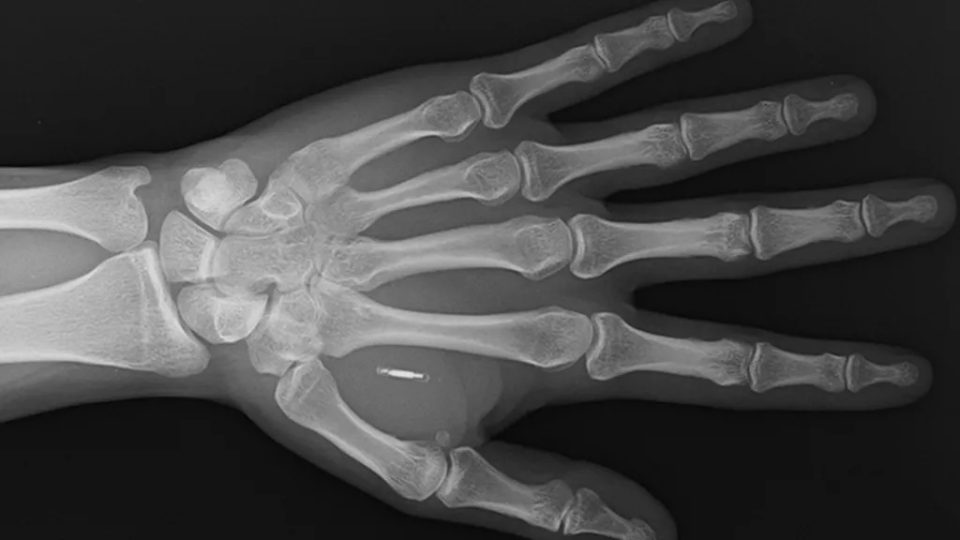

Facebook’ta paylaştığı bir gönderi ve elinin röntgen görüntüsüyle durumu kamuoyuna taşıyan Wang, “Şu anda kendi bedenimin içindeki teknolojiye erişemediğim, tamamen kendi hatamdan kaynaklanan küçük bir siberpunk distopyası yaşıyorum” ifadelerini kullandı. Bu samimi itiraf, kişisel teknoloji entegrasyonunun komik olduğu kadar düşündürücü yanını ortaya koydu.

Wang’ın hikayesi yıllar önce, sahne şovlarını daha etkileyici kılmak amacıyla başladı. RFID (Radyo Frekansı Tanımlama) çipi olarak bilinen minik cihazı, elinin başparmak ve işaret parmağı arasındaki deri altına enjekte ettirdi. Amacı, seyircilerin telefonlarını eline yaklaştırdığında tetiklenen “modern” sihir numaraları yaratmaktı.

Sahne kullanımından vazgeçen Wang, çipi yeniden programlayarak bir Bitcoin cüzdan adresi ve popüler görsel paylaşım sitesi Imgur’daki bir meme görseline yönlendiren bir link ile ilişkilendirdi. Fakat birkaç yıl sonra Imgur linki geçersiz hale geldi. Wang çipi güncellemek veya yeni bir işlev yüklemek istediğinde ise karşısına aşılması zor bir engel çıktı: Çipi programlamak için kullandığı şifreyi tamamen unutmuştu.